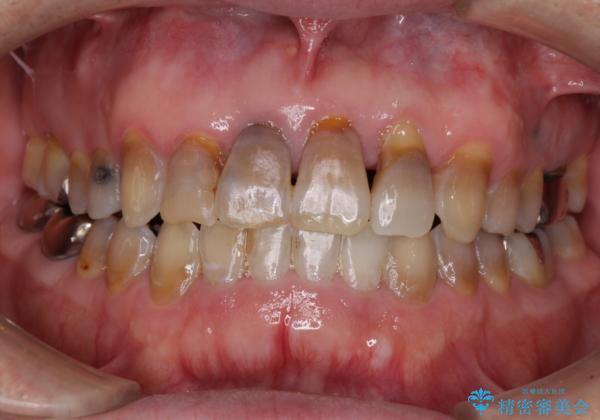

上顎の狭窄歯列 インビザラインによる拡大矯正

- 前歯の叢生と臼歯のクロスバイトを気にして来院された患者様です。

急速拡大装置による上顎の側方拡大を行い、その後はインビザラインより歯列を改善することとしました。

20代後半以降の男性は上顎骨の側方拡大処置の成功率が低く、今回も骨を拡大することができませんでした。

しかしながら、歯列を側方に拡大することができ、その後はインビザラインにて叢生を解消することができました。